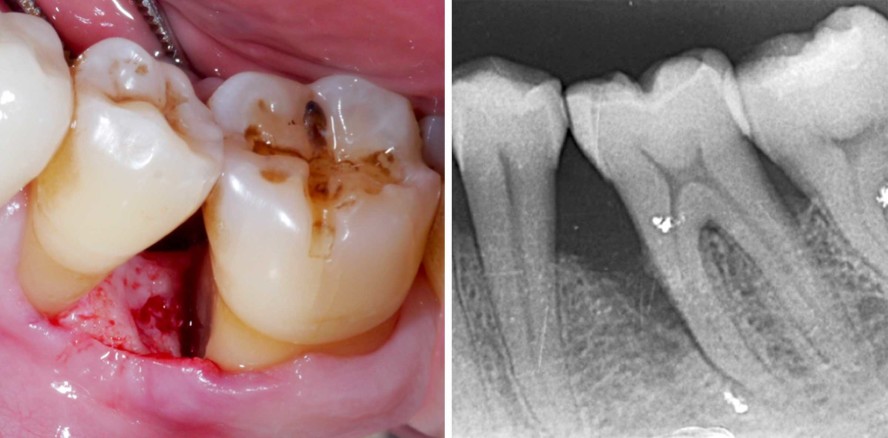

Foto: © Priv.-Doz. Dr. Kristina Bertl

Ausgedehnte parodontale Defekte müssen daher oft zusätzlich mit resektiven oder regenerativen Techniken behandelt werden, um das Risiko für Restsondierungstiefen im Vergleich zu einer alleinigen nichtchirurgischen Therapie als auch im Vergleich zu einer nichtchirurgischen Therapie in Kombination mit einem OFD zu reduzieren. Resektive Therapieansätze haben jedoch den Nachteil, dass sie zu größeren gingivalen Rezessionen, eventuell zu einem zusätzlichen Attachmentverlust und oft zu einem unästhetischen Ergebnis führen.6–8 Hier setzen vor allem bei Zähnen mit tiefen vertikalen Knochendefekten die regenerativen parodontalen Verfahren an. Diese Verfahren haben das Ziel, durch den Einsatz von Biomaterialien (z. B. Membranen, Wachstumsfaktoren, Augmentationsmaterialien etc.) signifikant bessere klinische (d. h. größerer Attachmentzugewinn, geringere Restsondierungstiefen und geringere gingivale Rezessionen) und radiologische Ergebnisse (d. h. größerer Knochenzugewinn und geringere Restdefekttiefe) zu erzielen (Abb. 1). Regenerative parodontale Verfahren – wie der Begriff schon sagt – führen auch zu signifikant besseren histologischen Ergebnissen im Vergleich zu konventionellen chirurgischen Verfahren, das heißt zu einer vermehrten Neubildung von Zement, parodontalem Ligament und Alveolarknochen, vorausgesetzt, dass eine korrekte Patienten- und Defektauswahl, korrekte Durchführung der Behandlung und ungestörte Wundheilung gewährleistet sind.9, 10

Die S3-Leitlinie Die Behandlung von Parodontitis Stadium I bis III gibt unter anderem auch einen Überblick über die empfohlenen Techniken und Materialien für die regenerative parodontale Therapie von tiefen vertikalen Knochendefekten.1, 11 Im Allgemeinen kann bei einer geringeren Restsondierungstiefe (d. h. < 6 mm) zunächst auch ein erneutes nichtchirurgisches Debridement in Betracht gezogen werden; ein regeneratives Vorgehen ist für vertikale Knochendefekte mit einer Restsondierungstiefe von ≥ 6 mm, einer intraossären Defekttiefe von zumindest 3 mm und bei optimaler häuslicher Mundhygiene empfohlen.1 Zum Einsatz sollten Schmelz-Matrix-Proteine (EMD; Abb. 2) oder Membranen zur gesteuerten Geweberegeneration (GTR; Abb. 3) mit oder ohne Augmentationsmaterial (autologer Knochen oder Knochenersatzmaterial) kommen.1, 11 Der Einsatz von Augmentationsmaterial kann in Abhängigkeit von der Anatomie und Wandigkeit des vertikalen Defektes gewählt werden, wobei Augmentationsmaterial vor allem bei einem Fehlen von ein bis zwei Wänden und/oder sehr weiten Defekten angedacht werden sollte (Abb. 4).12, 13